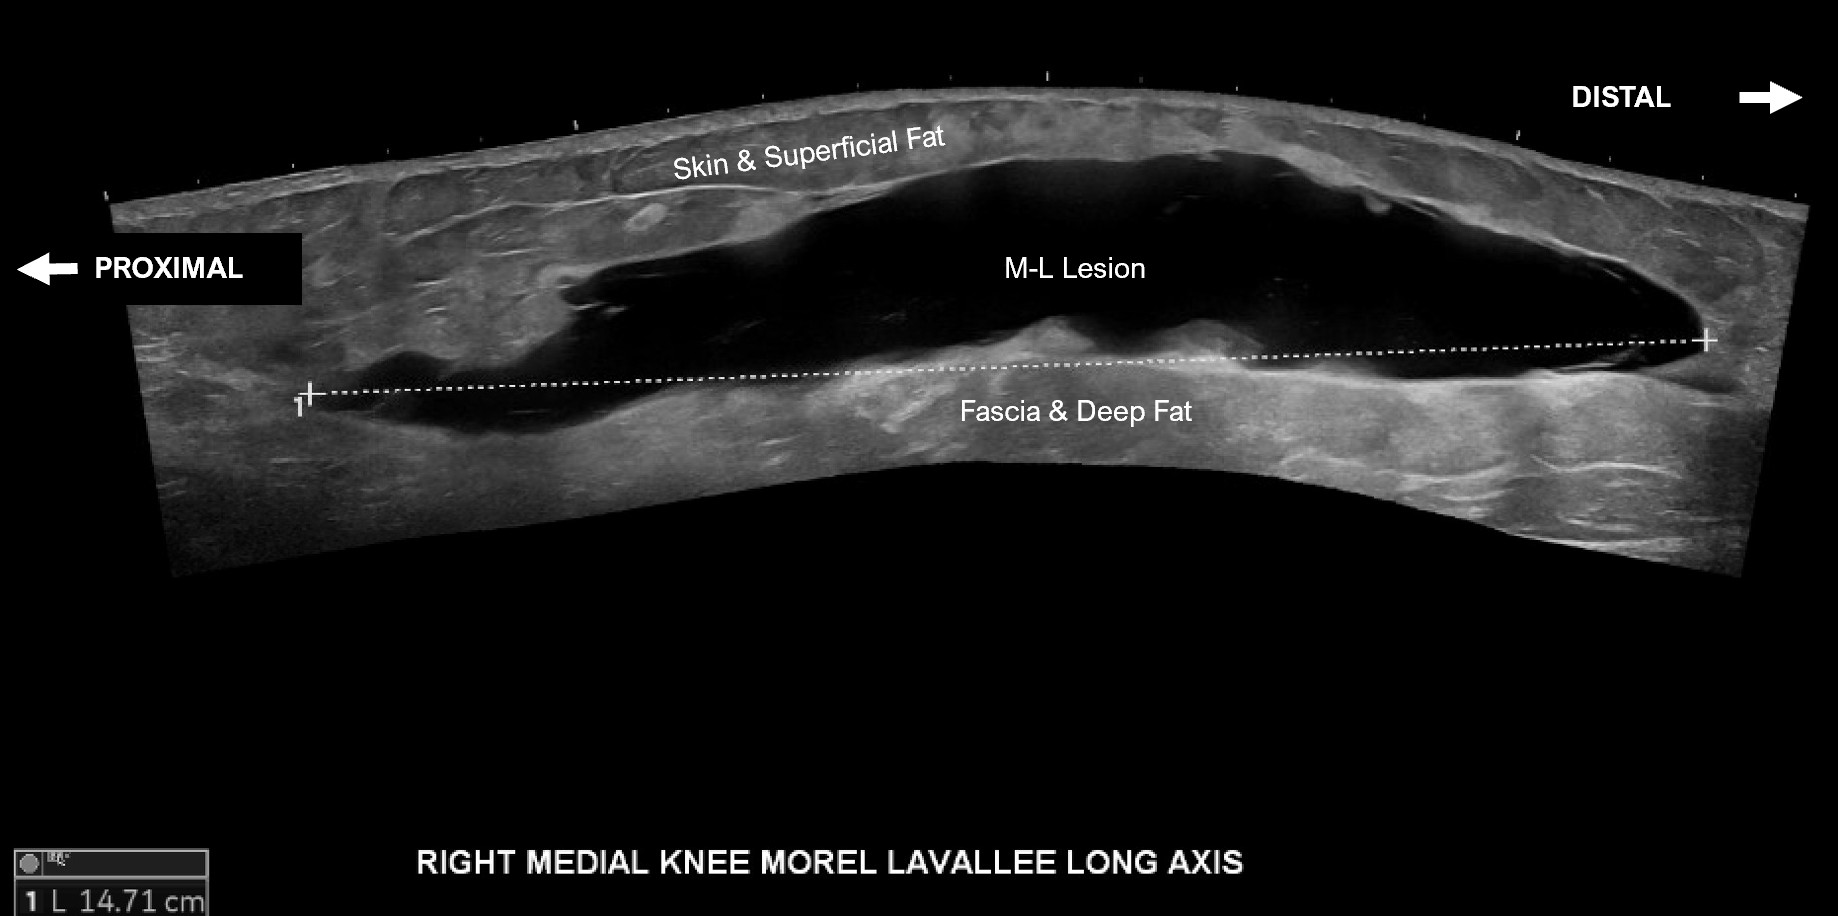

Unlabeled long axis extended view of the medial distal thigh and knee with evidence of a Morel-Lavallee lesion measuring approximately 14.7 cm from proximal to distal.

Labeled long axis extended view of the medial distal thigh and knee with evidence of a Morel-Lavallee lesion between the skin and superficial fat and the fascia and deep fat measuring approximately 14.7 cm from proximal to distal.